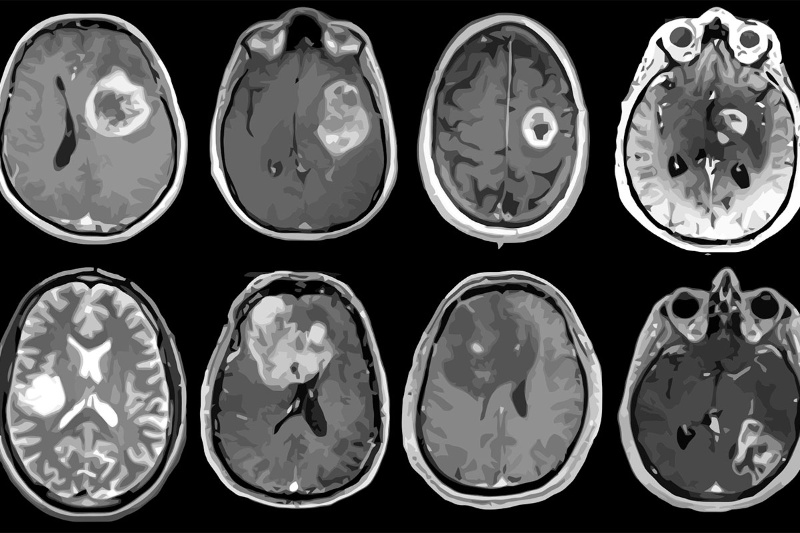

وقتی ابتلای لوکاس در سن ۶ سالگی به نوع نادری از تومور مغزی تشخیص داده شد، هیچ شکی در مورد پیشرفت بیماری وی در آینده وجود نداشت. ژاک گریل، پزشک فرانسوی وقتی بهیاد میآورد که باید به والدین لوکاس بگوید او قرار است بمیرد، احساساتی میشود. بااینحال ۷ سال پس از آن روزها، اکنون لوکاس ۱۳ ساله شده است و اثری از تومور در مغز او نیست.بهگفتهی محققانی که لوکاس را معالجه کردهاند، این پسر بلژیکی نخستین کودک در جهان است که از گلیومای ساقهی مغز (نوعی سرطان بیرحم) جان سالم به در برده است. گریل، رئیس برنامهی تومور مغزی در مرکز سرطان گوستاو روسی در پاریس، معتقد است که لوکاس برای زنده ماندن تمام مشکلات سر راه را شکست داد. این بیماری که نام کامل آن گلیوم پونتین داخلی پراکنده (diffuse intrinsic pontine glioma) یا بهاختصار DIPG است، هرساله در حدود ۳۰۰ کودک در ایالات متحده و تا ۱۰۰ کودک را در فرانسه درگیر میکند. تنها ۱۰ درصد از کودکان دو سال پس از تشخیص تومور زنده میمانندجامعه پزشکی در آستانهی روز جهانی سرطان کودکان در پنجشنبهی گذشته، پیشرفتهایی را ستایش کرد که بهلطف آنها درحالحاضر ۸۵ درصد از کودکان، بیش از ۵ سال پس از تشخیص سرطان زنده میمانند؛ اما چشمانداز کودکان مبتلا به DIPG تأسفبار است و بیشتر آنها یک سال پس از تشخیص جان خود را از دست میدهند. مطالعهی اخیر نشان میدهد که تنها ۱۰ درصد از کودکان دو سال پس از تشخیص تومور زنده میمانند.رادیوتراپی گاهی اوقات میتواند سرعت حرکت سریع تومور را کاهش دهد؛ اما هیچ دارویی برای مقابله با آن مؤثر نبوده است.کپی لینکمورد مشابه دیگری وجود نداردلوکاس و خانوادهاش از بلژیک به فرانسه سفر کردند تا بتوانند یکی از نخستین بیمارانی باشند که به آزمایش BIOMEDE میپیوندند. این آزمایش، داروهای جدید بالقوه را برای DIPG آزمایش میکند. لوکاس از همان ابتدا بهشدت به داروی سرطان اورولیموس که بهطور تصادفی به او اختصاص داده شده بود پاسخ داد. گریل به خبرگزاری فرانسه میگوید: «در طول یکسری اسکن MRI شاهد ناپدیدشدن کامل تومور بودم.» با وجود نتایج بهدستآمده، پزشک معالج جرئت نکرد که رژیمدرمانی بیمار را حداقل تا یکسالونیم و پس از اعتراف لوکاس در خصوص مصرفنکردن داروها قطع کند. گریل در ادامه میافزاید: «من هیچ مورد دیگری مانند او در دنیا نمیشناسم.»اینکه چرا لوکاس بهطور کامل بهبود یافته است و چگونه مورد او میتواند به کودکان دیگر که در وضعیت مشابه قرار دارند کمک کند، چیزی است که باید منتظر ماند و دید. هفت کودک دیگری هم که در این آزمایش شرکت داشتند، سالها پس از تشخیص بیماری زنده ماندند؛ اما فقط تومور لوکاس بود که بهطور کامل ناپدید شد. به باور گریل دلیل اینکه این کودکان به داروها پاسخ میدهند، درحالیکه دیگران پاسخ نمیدهند احتمالاً به ویژگیهای بیولوژیکی تومورهای آنها بستگی دارد. او در ادامه میگوید: «تومور لوکاس دارای یک جهش بسیار نادر بود که به اعتقاد ما سلولهای آن را نسبت به دارو حساستر میکرد.»کپی لینکبهدنبال لوکاسهای بیشترمحققان در حال مطالعهی ناهنجاریهای ژنتیکی تومورهای بیماران و همچنین ایجاد ارگانوئیدهای توموری هستند که تودههایی از سلولهای تولیدشده در آزمایشگاه محسوب میشوند. ماری آن دبیلی، محققی که بر کار آزمایشگاه نظارت دارد، میگوید: «پروندهی لوکاس امید واقعی دارد. ما سعی خواهیم کرد تا تفاوتهای شناساییشده در سلولهای لوکاس را در آزمایشگاه بازتولید کنیم.»تیم تحقیقاتی قصد دارد با بازتولید تفاوتهای ژنتیکی سلولهای لوکاس در ارگانوئیدها ببیند که آیا میتوان تومور را بههمان اندازه که در مورد لوکاس اتفاق افتاد ازبین برد یا خیر. دبیلی گفت: «اگر این کار مؤثر باشد، گام بعدی یافتن دارویی خواهد بود که تأثیر مشابه این تغییرات سلولی را روی سلولهای تومور داشته باشد.»بیشتر بخوانیدکاهش اندازه تومور مغزی با استفاده از کلاه مغناطیسی8 مرداد 00مطالعه ‘3یافتهای غیرمنتظره؛ گیاهان ممکن است کلید درمان سرطان در انسان باشند14 تیر 01مطالعه ‘4محققان با وجود داشتن هیجان زیاد درمورد سرنخ جدید، روی این نکته تأکید دارند که هنوز راه زیادی تا درمان احتمالی داریم. گریل در این مورد میگوید: «بهطور متوسط از نخستین سرنخ تا تبدیل شدن به دارو، ۱۰ تا ۱۵ سال طول میکشد که فرایندی طولانی و زمانبر است.»